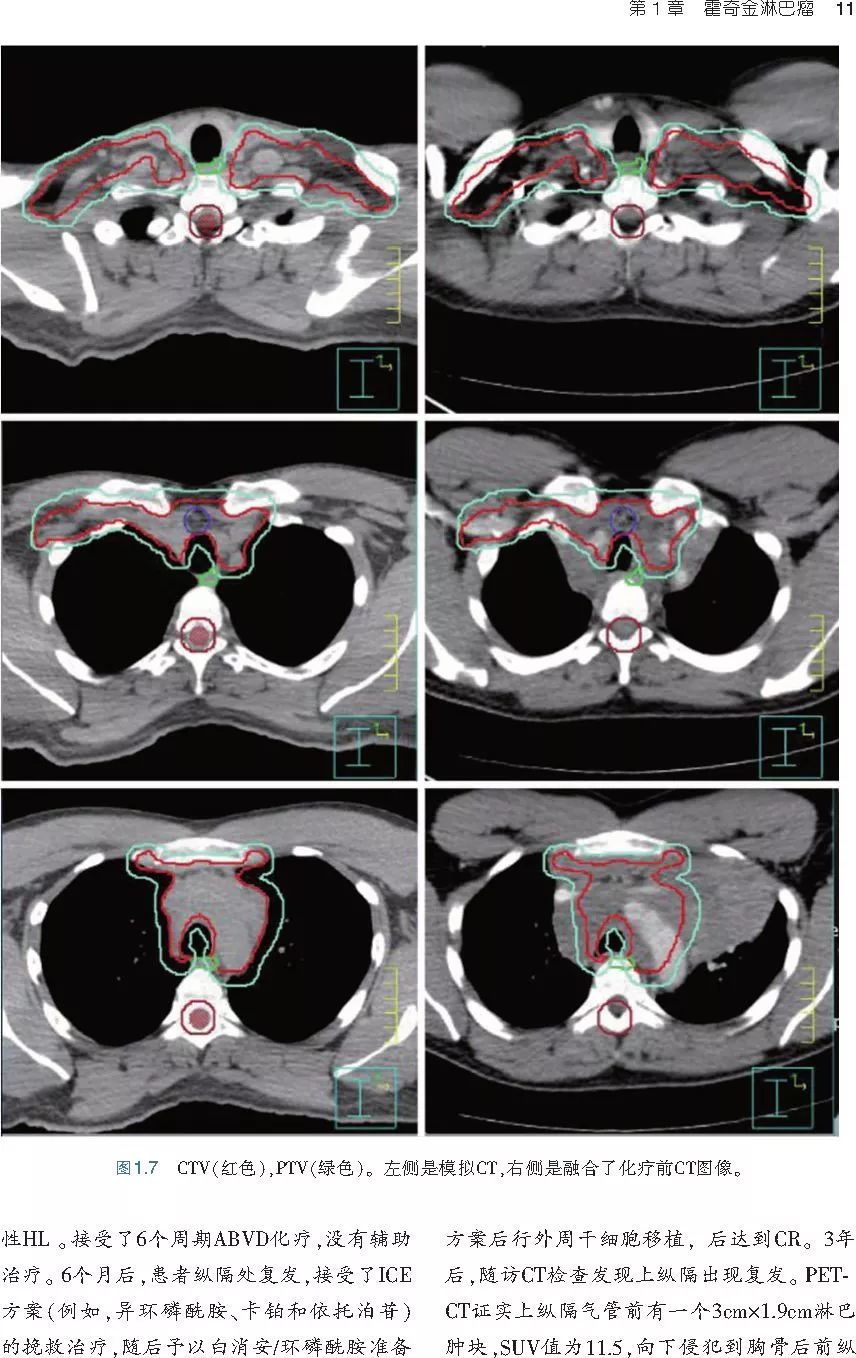

本书旨在帮助临床医生对常见血液系统恶性肿瘤疑难病例进行管理,包括霍奇金淋巴瘤、非霍奇金淋巴瘤和白血病患者,并通过多个病例进行阐述。案例讨论遵循标准格式,包括临床描述,其次是与诊断相关的病理描述和分期,然后详细讨论治疗选择。最后,确定治疗方案,并提供所使用的规划放疗技术/方式的图像。对放射肿瘤医生进行临床决策非常有帮助,针对血液病临床医生也有很好的指导作用。

近年来,放射治疗技术得到了迅速发展,调强放疗、图像引导放疗及其他新技术方法等,对恶性肿瘤治疗产生了巨大影响。现代放疗技术使精确定位、靶区勾画及给量成为可能,实现了肿瘤局控率和生活质量的双赢,对血液系统恶性肿瘤的临床治疗也产生了一定的影响。此书内容上不仅反映了血液系统恶性肿瘤综合治疗的进步,更是对其中放射治疗的新变化进行了系统、详细的阐述,这对当前血液系统恶性肿瘤放射治疗临床实践具有非常好的指导作用和参考价值。